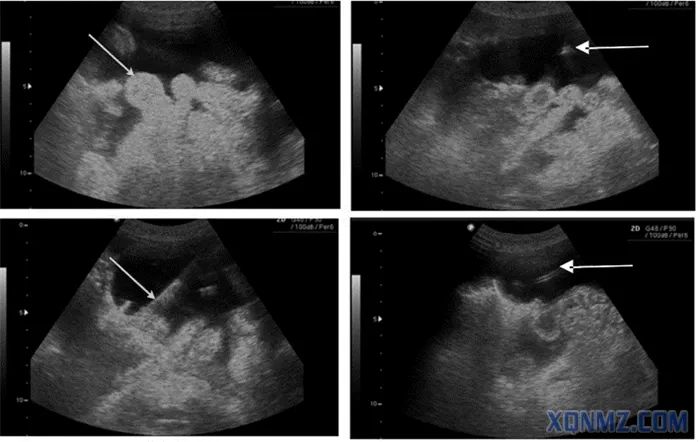

超声引导下腹腔穿刺术

(腹水中漂浮的肠袢(左上),箭头所示;穿刺针尖(右上);置入导丝(左下);置入导管(右下))

大量腹水引起腹部不适,如伴发腹水感染或影响呼吸或静脉回流,则危及生命。床旁超声指导穿刺抽液,可减少医源性损伤。超声探头多选择腹部探头。超声定位并标记腹腔穿刺点,一般选择“反麦氏点”或腹水最深处,且避开腹内脏器、如漂浮的肠管、膀胱、肝脾等。整个操作过程中都在超声引导下进行。针尖及导丝一旦进入无回声的液体区时就可表现为强回声影。【3】